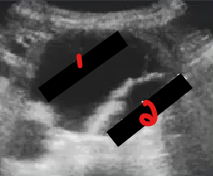

Label the crossed-out structures seen on this image.

IVC

RRA

Aorta

LRA

LRV